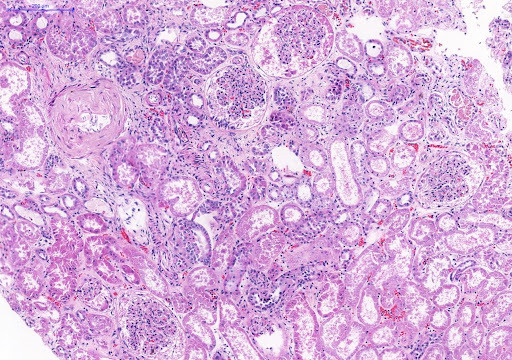

Sistema urinário.

O SARS‐CoV‐2 infecta células dos glomérulos e túbulos renais e causa um tipo particular de glomeruloesclerose segmentar e focal (glomerulopatia colapsante) e microangiopatia trombótica

túbulos mostram dilatação, degeneração vacuolar, redução da borda em escova e necrose de células nos túbulos proximais

Focos de infiltrado inflamatório mononuclear e de fibrose também podem ser observados.

Foco de necrose pode ocorrer em consequência da vasoconstrição intensa induzida pela Angiotensina II.